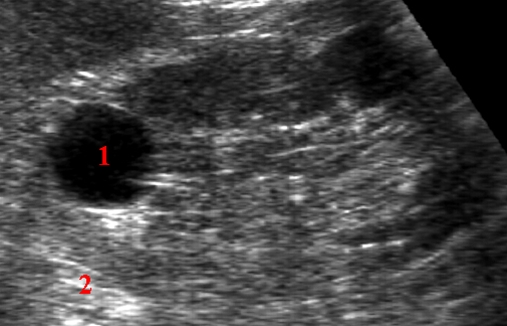

Ultralydsundersøgelse af en nyre.

Svarende til øvre nyrepol ses en mørk lav-ekkogen, rund og velafgrænset homogen cyste (1). Bag den simple godartede cyste frembringes en ekkoforstærkning i form af et lysere område (2).